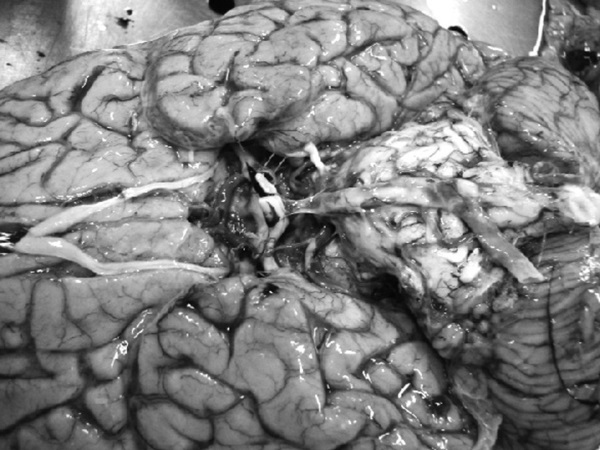

На секции был установлен следующий диагноз.

Основной:

1. Последствия инфаркта головного мозга. Внутренняя гидроцефалия. Атеросклероз артерий виллизиева круга.

2. ИБС. Постинфарктный кардиосклероз. Атеросклероз коронарных артерий.

Фоновый:

1. Артериальная гипертензия.

2. Гипертрофия левого желудочка сердца.

Осложнения:

1. Длительная иммобилизация.

2. Хроническая сердечная недостаточность.

3. Невроангиосклероз.

4. Пролежни.

5. Интоксикация.

6. Отек головного мозга.

Сопутствующий:

Доброкачественная гиперплазия предстательной железы

Последствия ОНМК: постинфарктные кисты головного мозга

Постинфарктный кардиосклероз

Атеросклероз сосудов головного мозга. Отек головного мозга

Атеросклероз коронарных артерий

Гипертрофия левого желудочка

Мускатная печень

Полнокровные легкие

Рис. 1. Результаты аутопсии больного 68 лет